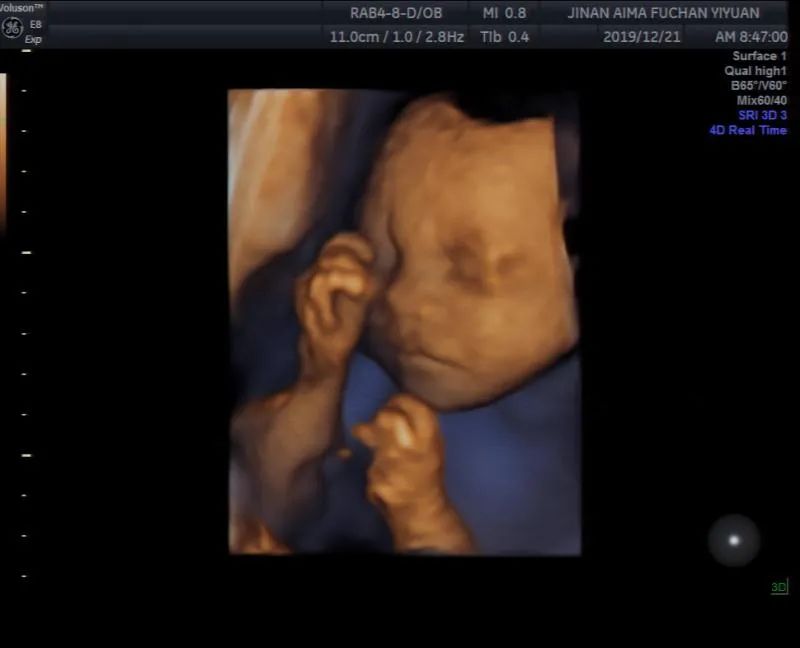

这是我的二胎宝宝

宝宝在肚子里面一直很好动

16周一过就能明显感觉胎动

这个过程最让我感动的是和他的交流

——30周左右脐带绕颈

我一直跟他讲要绕回来

后面他果然自己绕回来了

32周的时候医生说胎位不正

我又给他做工作

教他把头向下摆正

他似乎真的能听懂我的话

不到一周胎位就正了

34周左右的时候B超照着说小了2周多

我叮嘱他好好吸收营养

孕晚期开始一点点改善

38周到了还没有入盆

天天跟他说要快点入盆

后面检查没过几天就真的入盆了